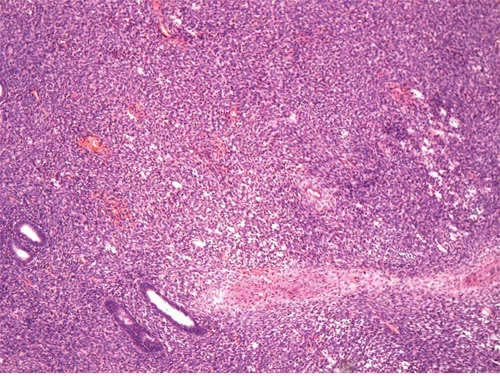

On microscopic examination, 9 cases showed features of low-grade ESS. The tumors were typically composed of sheets of small, closely pack cells resembling the stromal cells of the proliferative endometrium, with scant cytoplasm and round to oval nuclei (Figure 1). Sex cord-like differentiation was observed focally in 2 cases. Five cases showed features of high-grade ESS. The tumors were characterized by a monomorphic proliferation of round cells, which were larger than those of low-grade ESS with increased cytoplasm and high-grade cytologic atypia (Figure 2). Three of the five cases of high-grade ESS had a component of low-grade ESS.

Figure 1: Low-grade ESS. The tumor is composed of generally uniform cells with scant cytoplasm and round to oval nuclei (original magnification × 400, hematoxylin-eosin stain).